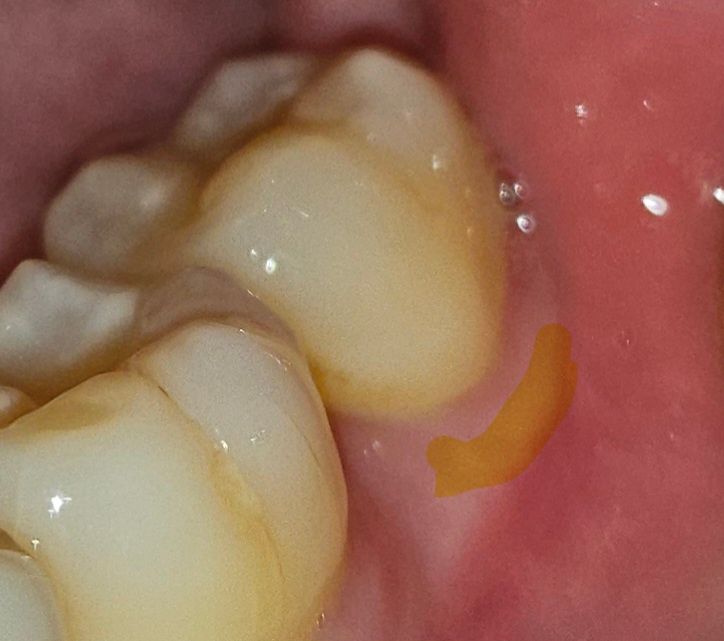

어금니 잇몸이 너무 내려가서 레진치료를 해야할까요?

어금니 잇몸이 너무 내려간거 같아요 잇몸이랑 치아가 닿은 그 부분이 아파요. 막 으아아악 이런 아픔이 아니라 약간 우리우리?

노란색 칠한 부분이 좀 많이 내려왔어요..

잇몸이 많이 내려가신거 같지는 않습니다. 일단은 지각과민제를 도포해보시고 그래도 불편하시면 레진으로 하시는게 좋을것같습니다.

잇몸이 별로 내려가지 않았습니다.

잇몸 높이는 거의 정상이라고 볼 수 있습니다.

사진으로만 봐서는 잇몸이 많이 내려간것으로 보이지는 않습니다.